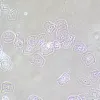

MAGUS SPH2 faasikontrastsuseadme koosneb faasikontrasti liugurite komplektist, faasikohustusega andurite komplektist ning keskendava teleskoobist. Faasikontrastsuseadet kasutatakse läbipaistvate madala kontrastsusega proovide uurimiseks, mis pole heledas väljavalguses nähtavad. Värvimine tapab elusaid rakke. Tehnika peamine eelis on see, et seda saab kasutada elusate värvimata organismide uurimiseks nende loomulikus olekus. Tehnikat kasutatakse meditsiinis, ökoloogias, farmakoloogias, põllumajanduses jne.

Faasikontrasti liugurid

Faasikontrasti liugur paigaldatakse kondensaatoripesasse. Liugur on plaat kahe auguga: vaba auk helevalguslikuks vaatluseks; teises augus on faasisisestus, mis vastab kasutatavale objektiivile. Faasikontrastsuseadmele kuulub kaks liugurit: ühel on sisestus, mis töötab koos 10x, 20x ja 40x objektiividega; teine sisestus töötab koos 100x objektiiviga. Sisestuse märgistus vastab kasutatavale objektiivile. Liugur võimaldab teil hõlpsasti üle minna helevalguslikult vaatluselt faasikontrasti tehnikale ja tagasi.